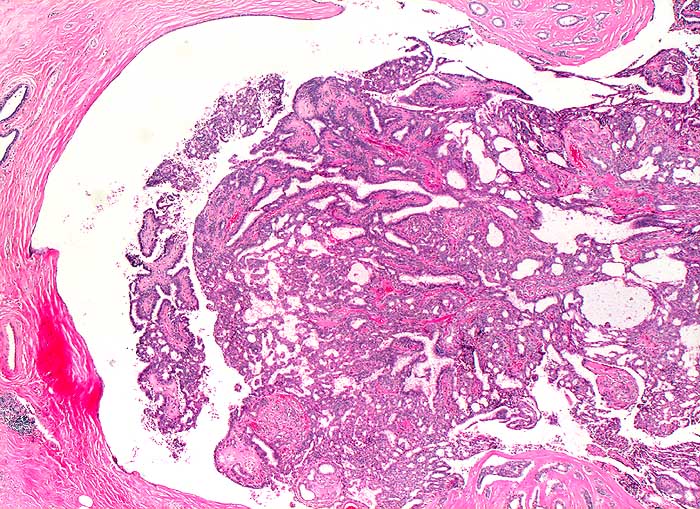

PathoPic ID 5689 - Milchgangspapillom

Milchgangspapillom

benigner Tumor

Mamma

Tubulopapillärer Tumor in einem ausgeweiteten Milchang.

Tastbefund rechts bei 12h, perimamillär mit benignen Schallkriterien. DD: Fibroadenom, Lipom, Fettgewebsnekrose.

Histologie

25

37